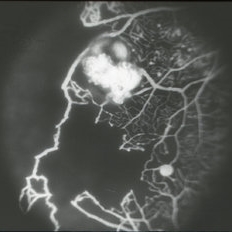

FA image of capillary non-perfusion and retinal angiomas of Von Hippel-Lindau OS.

Condition/keywords: fluorescein angiogram (FA), Von Hippel-Lindau